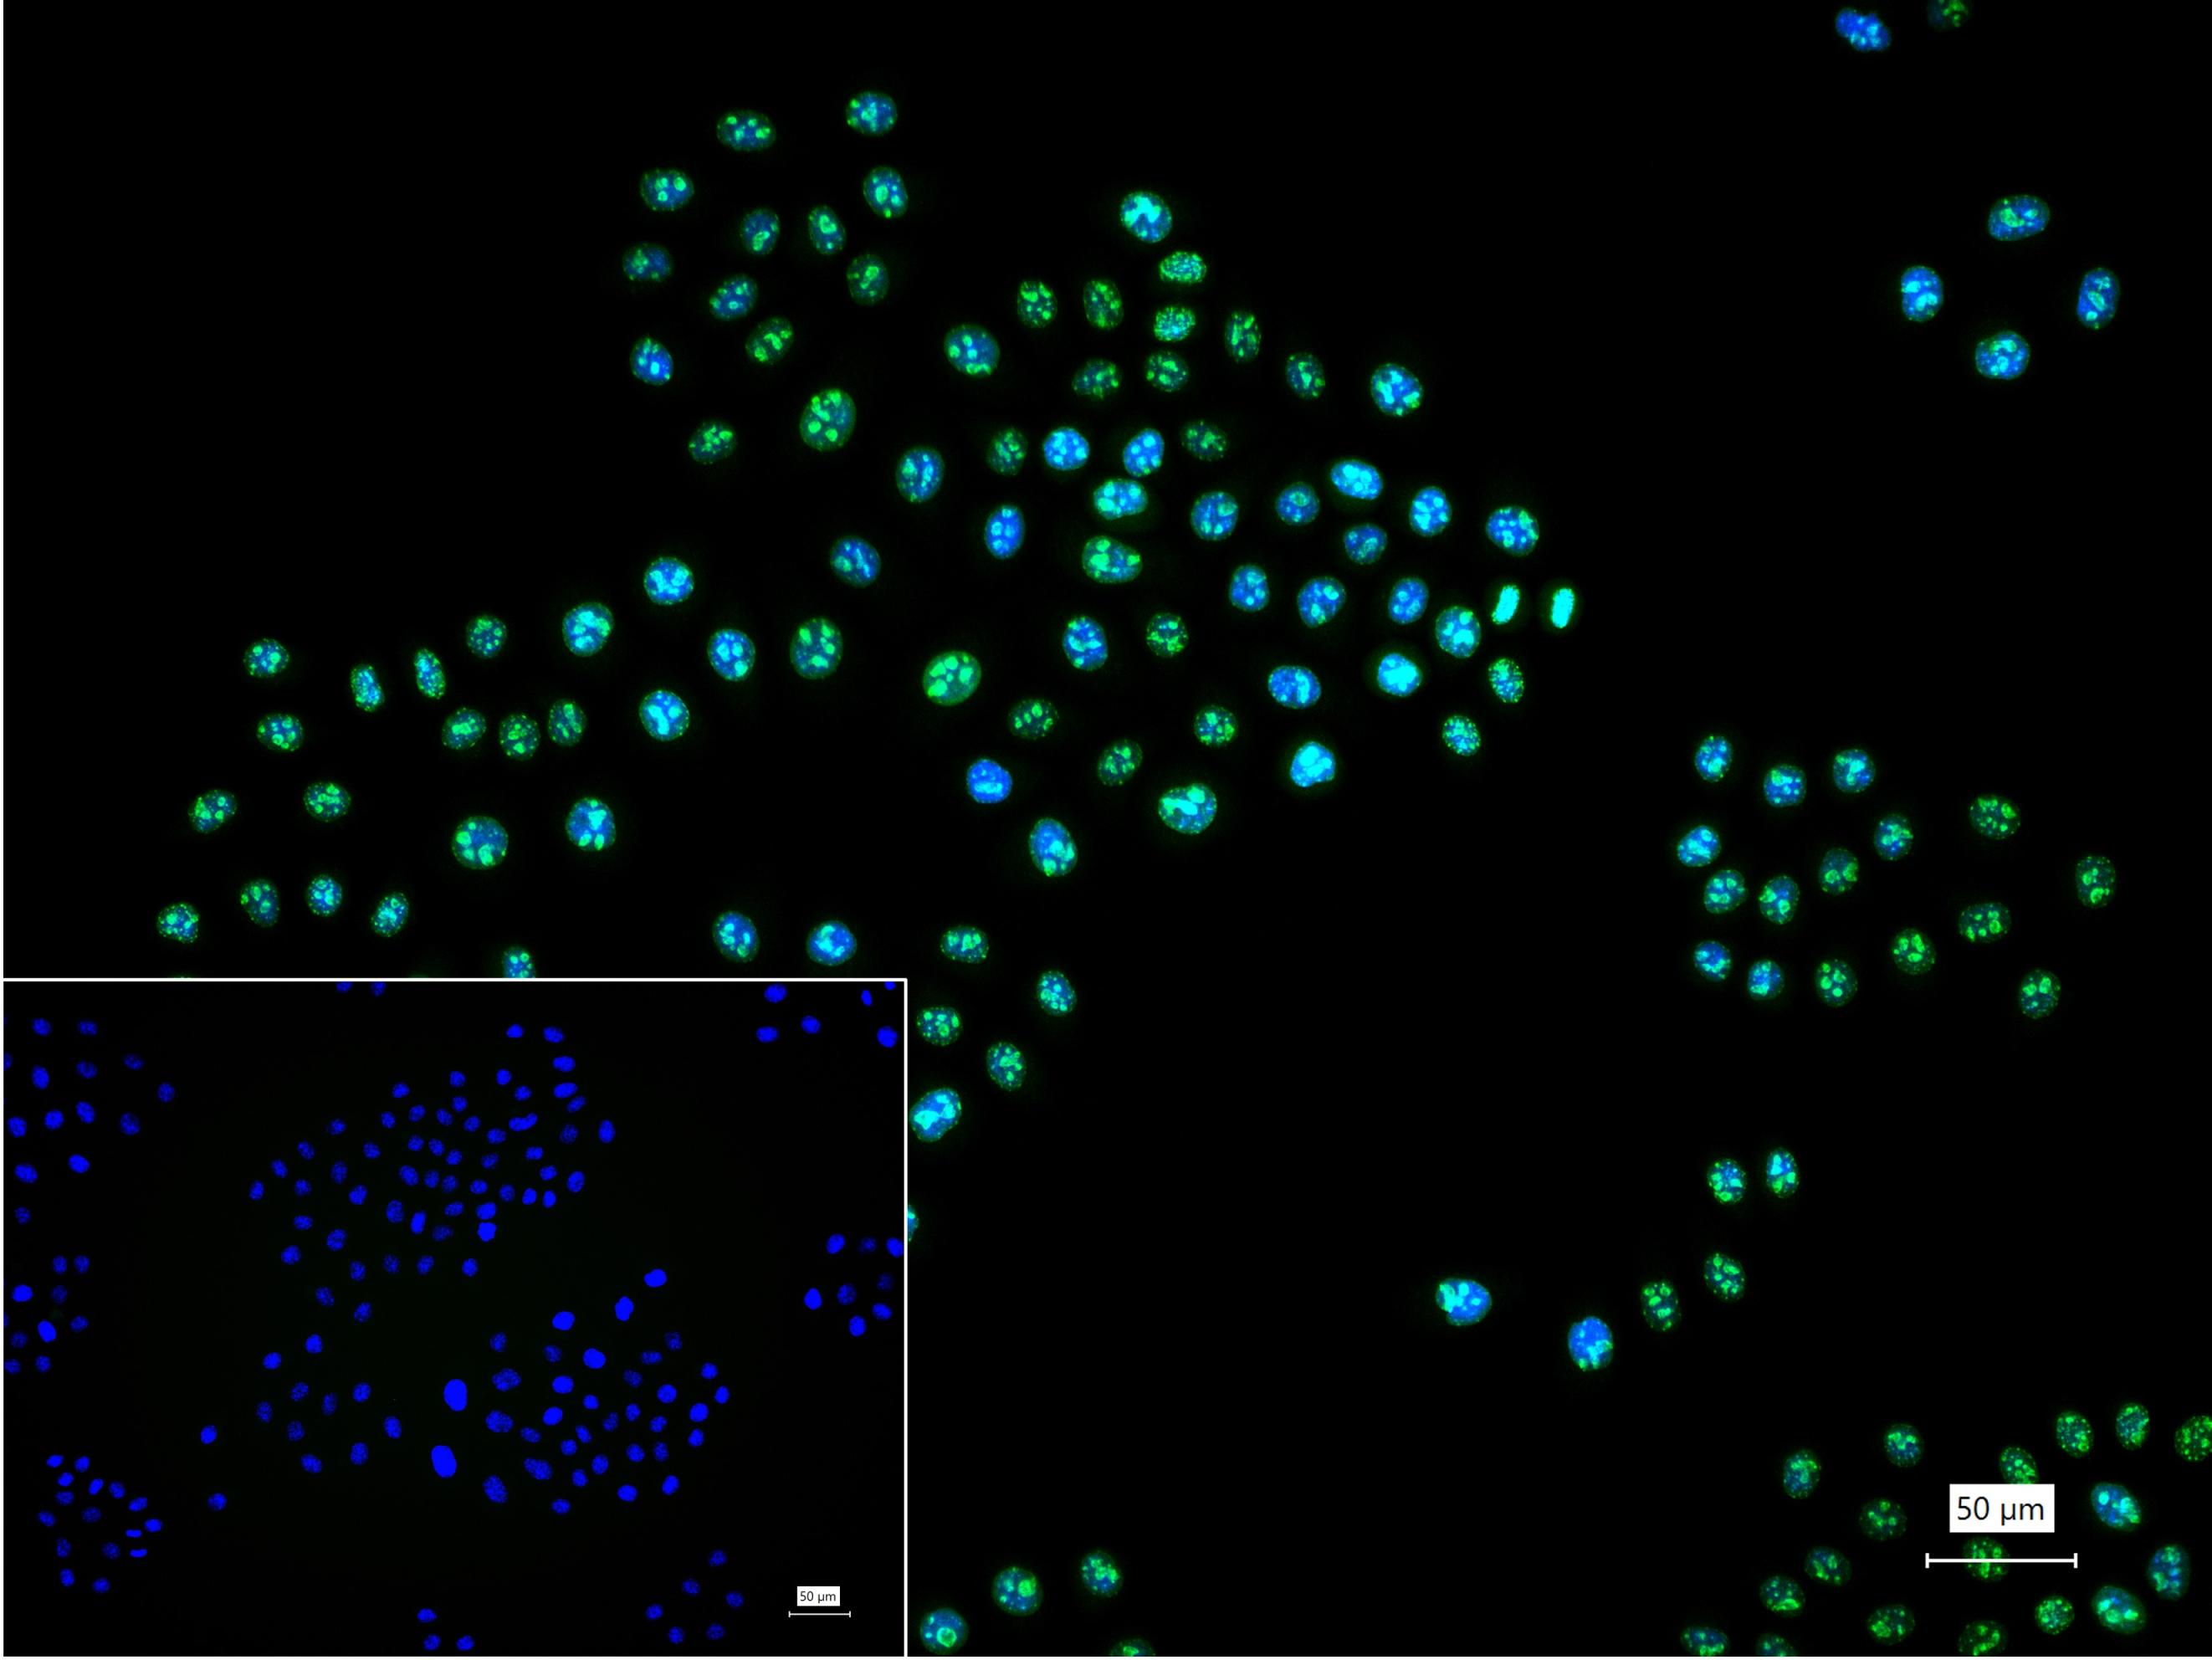

产品应用 Flow-Cyt=1:50-100,ICC/IF=1:100-500

4% Paraformaldehyde-fixed Hela (H) cell; Triton X-100 at r.t. for 20 min; Antibody incubation with (Ki-67) polyclonal Antibody, unconjugated (bs-23103R) 1:100, 90 min at 37°C; followed by conjugated Goat Anti-Rabbit IgG antibody (green, bs-60295G-BF488) at 37°C for 90 min, DAPI (blue, C02-04002) was used to stain the cell nuclei. PBS instead of the primary antibody was used as the blank control.